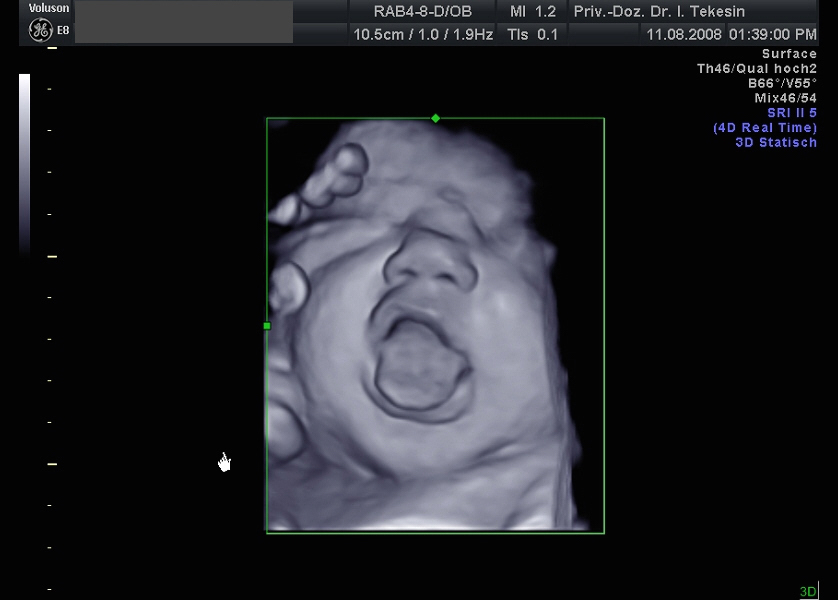

Ein freches Kind in der 38. Woche (3D-Darstellung)